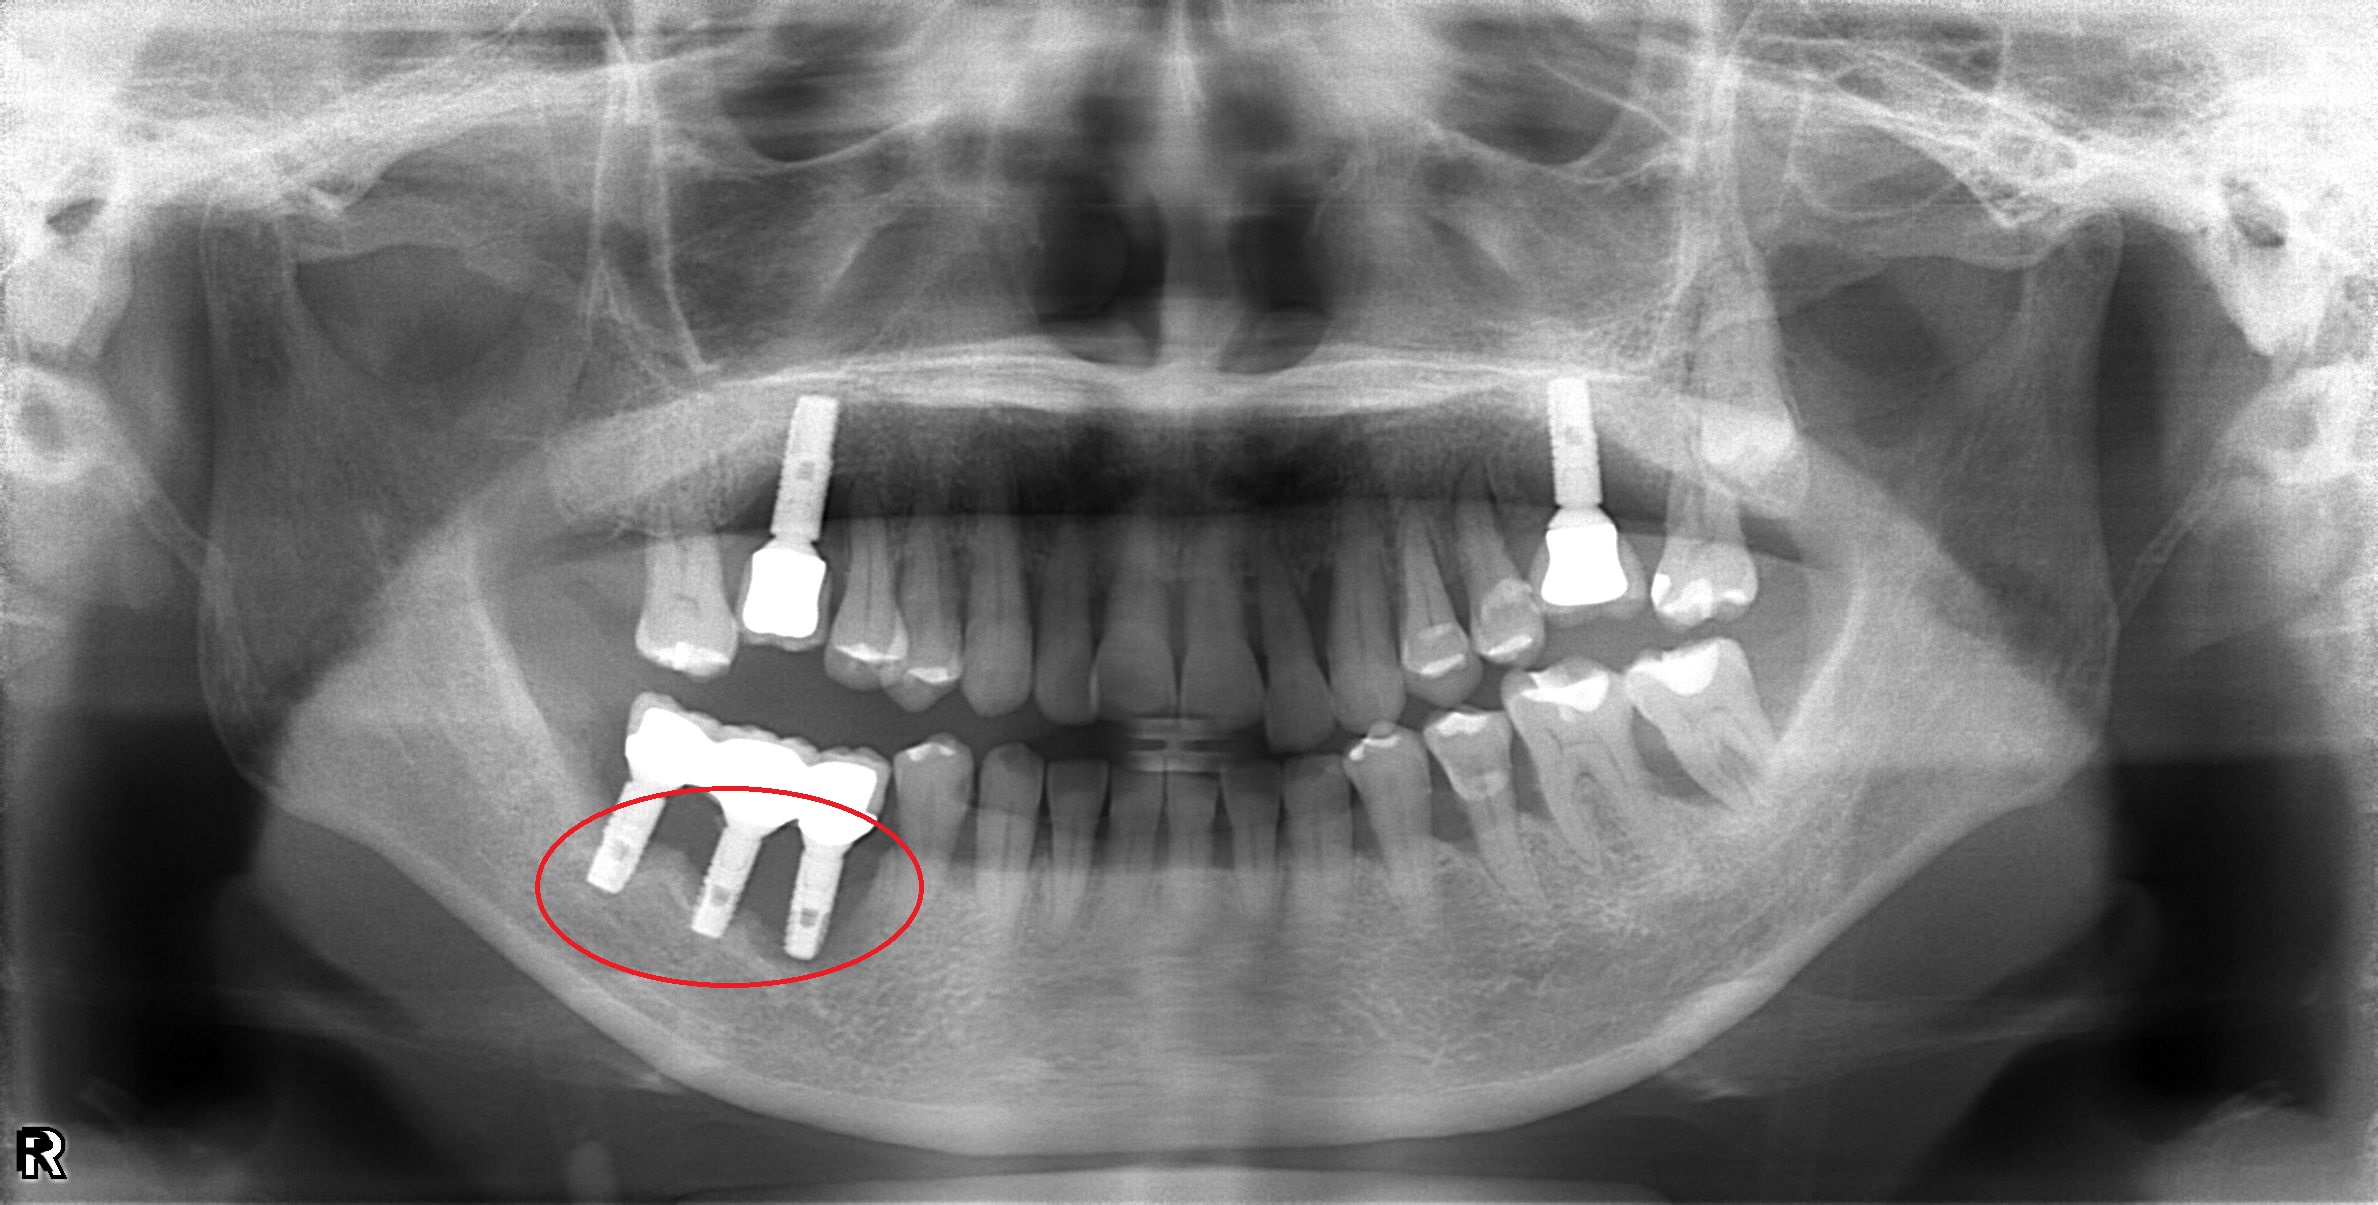

植體周圍炎處理

案例二